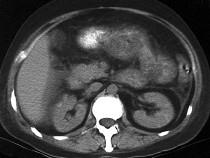

问题 男,32岁,阵发性腹痛、腹胀,伴恶心、呕吐,腹部可触及包块,影像检查如图,最佳的诊断是什么 ( )

选项 A.小肠肿瘤 B.麻痹性肠梗阻 C.空肠套叠 D.回肠套叠 E.结肠套叠

答案 C